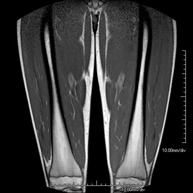

Exploració per estudiar la musculatura i dels tendons que s'originen en aquest nivell, com els tendons isquiotibials, lesió sovint en esportistes. La durada aproximada és de 16 minuts. No empra radiació ionitzant. - RM de Cuixa

Exploració ideal per estudiar les lesions en músculs isquiotibials i quàdriceps, sovint lesionats en esportistes. També permet una bona valoració de tendons i de nervis perifèrics. La durada aproximada és de 20 minuts. No utilitza radiació ionitzan. - RM de Genoll